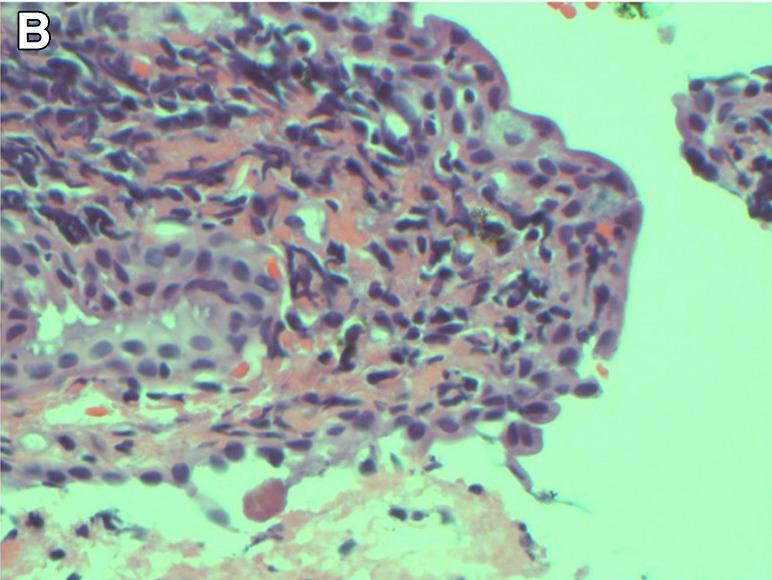

Η Τερέζα και η Δρ Ντάνα Ρόμπεϊ έδωσαν στη δημοσιότητα τις φρικτές εικόνες για να δείξουν τους κινδύνους του να μην αφαιρείται τη μάσκαρα το βράδυ πριν πέσετε για ύπνο

Η Δρ. Ρόμπεϊ, που δημοσίευσε μια μελέτη για την περίπτωση της Τερέζα, είπε πως δεν είχε ξαναδεί και παρόμοιο και πως κινδύνευε να μείνει τυφλή και πρόσθεσε πως ελπίζει ότι η περίπτωση αυτή θα είναι μια σημαντική πλατφόρμα για την ευαισθητοποίηση σχετικά με τους κρυφούς κινδύνους των καθημερινών προϊόντων ομορφιάς.